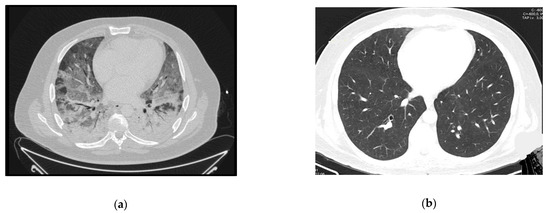

A 64-year-old woman with a history of hypertension, dyslipidemia and chronic pulmonary disease presented at the ER with fever, shortness of breath and a worsening cough despite a previous complete course of antibiotics for presumed CAP. She was hypoxic, with isolated elevation of CRP and diffuse ground-glass opacities on thoracic CT-scan (Figure 2a). Her status deteriorated despite antibiotics and oxygen supplementation in the Intermediate Care Unit, so she was transferred to the ICU and intubated. Three days after IMV and prone positioning, she was connected to VV-ECMO due to refractory respiratory acidemia. Anti-HIV testing was positive. Immune and viral study revealed severe immunosuppression (9 CD4+/mm3) and high serum viral load (4.050.000 copies/mL) and TMP-SMX plus corticosteroids were started for presumed PJP, at the recommended PJP treatment dosage. Diagnosis was confirmed by positive immunofluorescence for P. jirovecii in BAL.

ECMO was discontinued after 10 days. During the weaning off invasive ventilation, there was recrudescence of ARDS with increased ventilatory parameters and need for prone positioning. Nosocomial infection was considered, broad spectrum antibiotics were started and bronchofibroscopy repeated, with persistently positive immunofluorescence for P. jirovecii and a positive polymerase chain reaction (PCR) for cytomegalovirus in BAL. She completed a total of 33 days of treatment with TMP-SMX and 21 days of ganciclovir with respiratory improvement and started ART. She was extubated after 83 days and was transferred to the ward after three months of ICU stay for muscular rehabilitation, without other dysfunctions.

Follow-up imaging can be seen in Figure 2b. She was transferred to a rehabilitation unit with a residual need of oxygen support (2 L per minute), from which she recovered after some months of pulmonary rehabilitation.

Figure 2. Case 2 thoracic CT-scan at diagnosis (a) and follow-up (b).